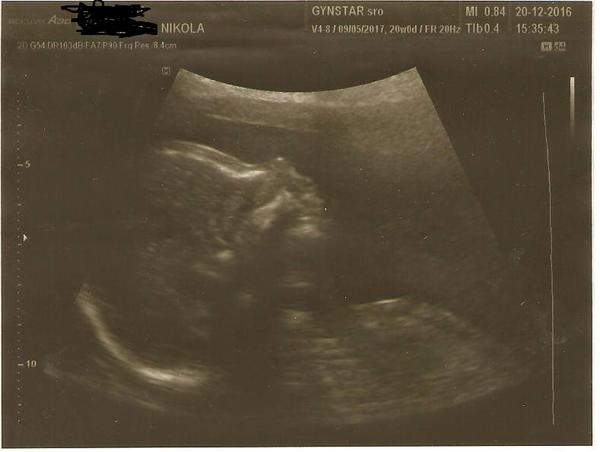

21. dec 2016

Ahojte snazilky chcem Vas trosku potesit 🙂 Bude to na 100% chlapcek takze Riško 🙂 Sme zdravucky a krasnucky 🙂 Prajeme Vam krasne sviatky a bohateho Jeziska 🙂 A mozno uz aj Vy dostanete najkrajsii darcek pod stromcek,vytuzene // 🙂 Drzime Vam prstiky 🙂